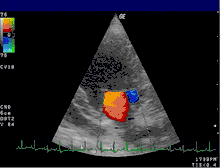

Цветовое доплеровское картирование (ЦДК)

Основано на кодировании в цвете значения доплеровского сдвига излучаемой частоты. Методика обеспечивает прямую визуализацию потоков крови в сердце и в относительно крупных сосудах. Красный цвет соответствует потоку, идущему в сторону датчика, синий — от датчика. Темные оттенки этих цветов соответствуют низким скоростям, светлые оттенки — высоким. Недостаток: невозможность получения изображения мелких кровеносных сосудов с маленькой скоростью кровотока. Достоинства: позволяет оценивать как морфологическое состояние сосудов, так и состояние кровотока по ним.

Кардиология, сосудистая и кардиохирургия

Эхокардиография (ЭхоКГ) — это ультразвуковая диагностика заболеваний сердца. В этом исследовании оцениваются размеры сердца и его отдельных структур (желудочки, предсердия, межжелудочковая перегородка, толщина миокарда желудочков, предсердий и т. д.), наличие и объём жидкости в полости перикарда, состояние клапанов сердца, а также, в допплеровском режиме, кровоток в сердце и магистральных сосудах. С помощью специальных расчетов и измерений эхокардиография позволяет определять массу миокарда, сократительную способность сердца (фракцию выброса, сердечный выброс и др.). Обычно ЭхоКГ проводится через грудную клетку (трансторакально), также существует чреспищеводная ЭхоКГ (ЧП-ЭхоКГ), когда специальный эндоскопический датчик помещается в пищевод. ЧП-ЭхоКГ позволяет лучше рассмотреть сердце, так как датчик располагается к сердцу ближе, чем при обычной ЭхоКГ и поэтому становится возможным использовать датчик с более высокой частотой ультразвука, что повышает разрешающую способность изображения. Также существуют специальные высокочастотные интраоперационные датчики, которые помогают во время операций на сердце.

4D-ЭхоКГ представленная на изображении, позволяет получать живое 3D-изображение сердца, то есть в реальном времени, что может быть также полезно, для проведения данной методики требуется специальный 4D-датчик.